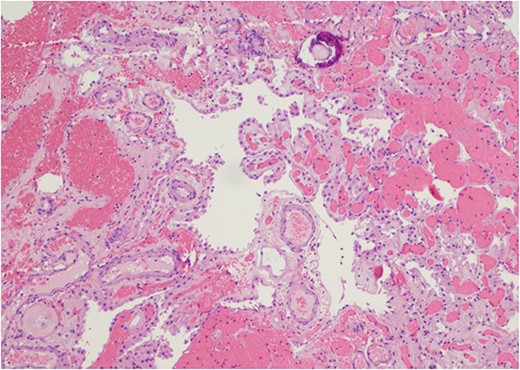

At her 12-week post-operative evaluation, follow-up MRI scans showed no residual or recurrent disease, as illustrated in Fig. 5. This patient’s genetic workup has demonstrated no propensity for neoplastic disease so far and she has resumed customary activities and routines.

(a) and (b) Stable postsurgical findings compatible with gross total resection of left atrial and adjacent periatrial tumor. No MRI evidence of residual/recurrent mass, with normal ventricular size.